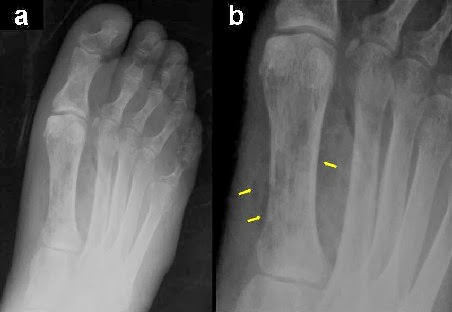

Radiografía de pie diabetico

La Radiología no es capaz de hacer Diagnóstico directo de diabetes como tal, pero el estudio radiológico a este nivel en el paciente diabético nos mostrará alteraciones tanto en partes blandas como en el tejido óseo, que son manifestación de los cambios fisiopatológicos sufridos en el pie.

Alteraciones en tejido óseo

• Infección ósea (osteomielitis)

• Cambios articulares y óseos neurotróficos, con atrofia, reabsorción y necrosis ósea eventualmente.

• Osteopatía diabética

• Neuroartropatia

Osteopatía diabética. Deformación y atrofia

RX pie diabetico. Degeneracion ósea en ante pie inferior

En la historia natural del pie diabético y formación del callo óseo intervienen, la insensibilidad del paciente a los microtraumatismos, la mala cicatrización de las heridas, la  alteración de la biomecánica del pie y la fricción en zonas concretas por la deformidad del pie, junto con el calzado inadecuado. La permanencia de ésta situación da lugar a la hipertrofia de la piel, pero esta hipertrofia no protege de la infección. Las deformidades, propiciadas por la atrofia y la neuropatía, las alteraciones articulares y el daño de tendones y ligamentos, determinan la localización del callo y la erosión cutánea:

ANTEPIE: la zona más frecuente de formación del callo es en la cabeza del 2º metatarsiano, pero también el la superficie plantar de las cabezas de los otros metatarsianos.

MEDIOPIE: se produce la deformidad “en mecedora” pudiendo formarse callo y úlcera en la superficie plantar del cuboides y en la cara dorsal de las bases de los metatarsianos subluxados.

RETROPIE: en la superficie plantar del aspecto posterior del calcáneo, en los maleolos. La ruptura del callo da lugar a la ulceración focal.

Por lo tanto, las úlceras se localizan en las áreas de mayor presión durante la deambulación y los microtraumatismos repetidos, siendo más prevalentes en las cabezas de primero y quinto metatarsianos, superficie plantar del segundo y tercer metatarsiano y superficie dorsal de los dedos; en el retropie, en el aspecto posterior del calcáneo y en el maleolo medial y lateral.